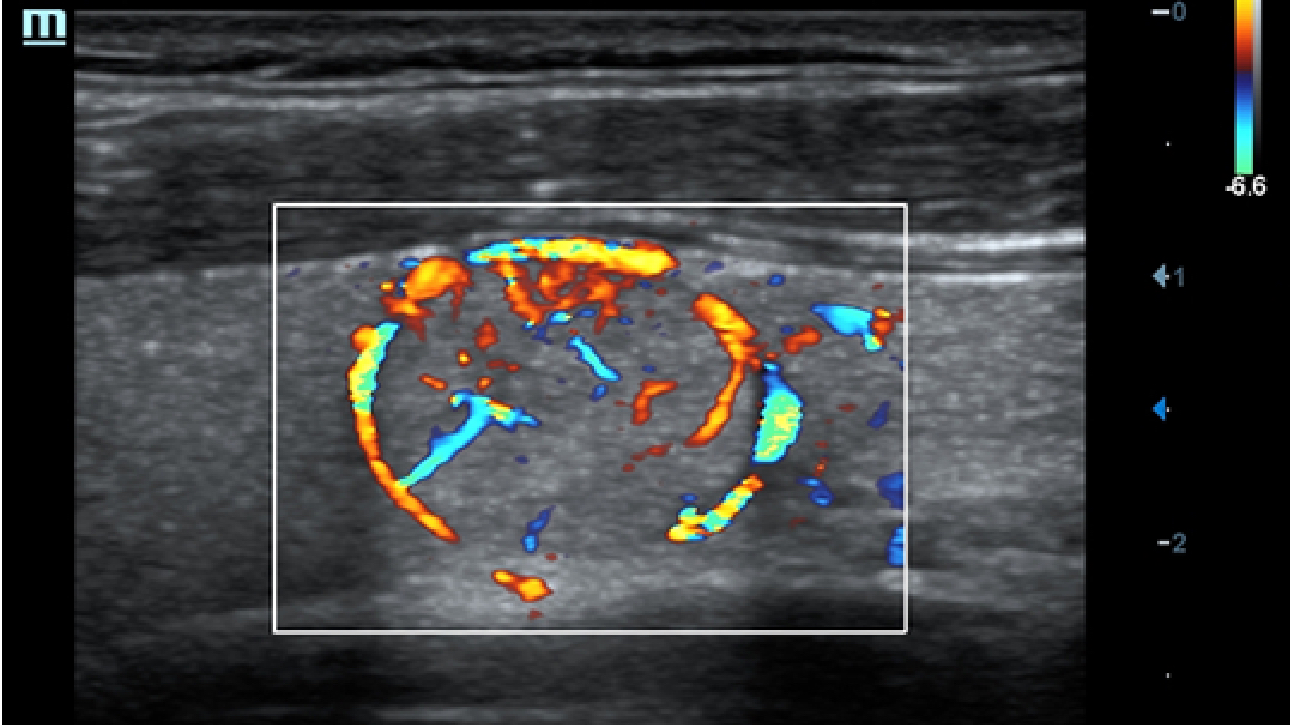

Klinische Bilder

Schallk?pfe